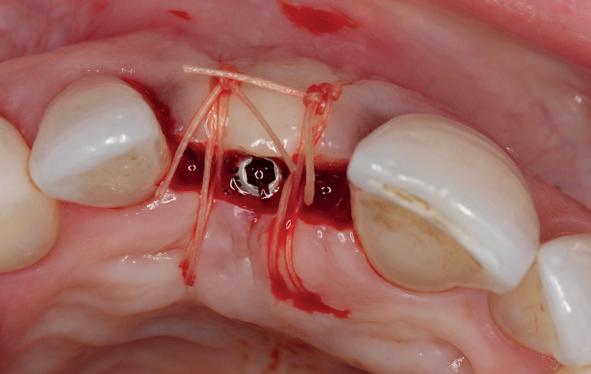

Implantologische behandelingen in het esthetische front vragen meer dan technische vaardigheid alleen. Ze vragen om overzicht, timing, vertrouwen en een team dat als vanzelf samenwerkt onder druk. Juist bij complexe casussen, waarin angst, infectie en hoge esthetische verwachtingen samenkomen, wordt zichtbaar hoe bepalend de rol van de tandartsassistent is.

Deze casus beschrijft een uitgebreide immediate implantaatbehandeling bij een patiënt die door meerdere collega’s werd geweigerd. Niet omdat de mogelijkheden ontbraken, maar omdat de complexiteit vroeg om een perfect afgestemde samenwerking. Het verhaal laat zien hoe de assistent in zo’n traject veel meer is dan een uitvoerende kracht of “mal”, maar een dynamische surgical guide die het proces mede stuurt, bewaakt en mogelijk maakt.De patiënt: wanneer alles samenkomt

Na het klinische onderzoek volgde het röntgenologisch traject. De CBCT liet precies zien wat we al vreesden: een front waarin het bot onregelmatig was, duidelijke radiolucenties rond de pijlers en een infectiegebied dat zich onder vrijwel de gehele brug had verspreid. Tegelijkertijd was er ook potentie. Net voldoende botstructuur om immediate implantaatplaatsing te overwegen, mits alles perfect gepland zou worden.